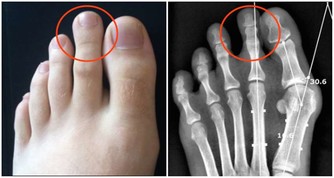

(三)瘀血

面色晦暗,呈黃褐色;

形體羸瘦,咋吃也不胖;

容易忘事、情緒煩躁抑鬱波動大;

常感到餓,剛吃過一頓,結果又餓了;

皮膚容易瘙癢、腹部痞硬隱痛、大便顏色經常偏暗偏黑。

瘀血產生的原因,一是外傷,比如流產、剖腹產。二是受寒或受熱:血得熱則行,得寒則凝。食冷飲冰,吹空調冷氣,單衣薄褲都是病因。不過熱邪損傷血脈,則血脈無以壅遏營血,血液失去運行之道而留止不行,也會成為瘀血。三是情緒不穩定造成的,若情志鬱結,氣機不暢,都會造成血液運行不暢。